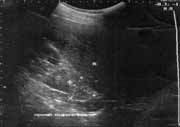

Эхоскопия сегодня - один из наиболее информативных и широкоиспользуемых лучевых методов диагностики. Благодаря простоте выполнения, высокой информативности, безвредности эхоскопия становится методом выбора уже на первом этапе применения инструментальных методов диагностики. Ультразвуковой метод исследования позволил существенно повысить процент ранней и точной диагностики опухолей надпочечников. С внедрением новейших аппаратов стало возможным зарегистрировать в надпочечнике любое объемное образование размером около 1 см. (Рис. 1), что по точности диагностики приближается к компьютерной томографии(1,2.5,6,7).

Рис. 1. Объемное образование до 1 см в диаметре в правом надпочечнике.